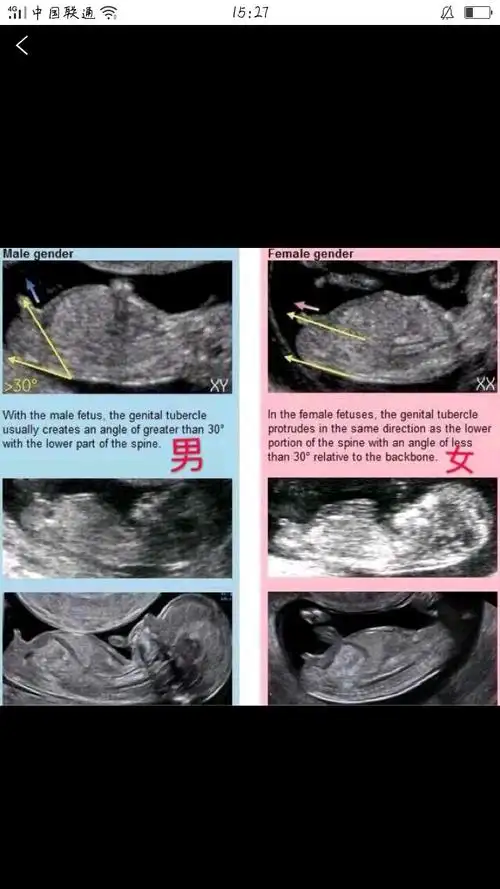

nt看男女